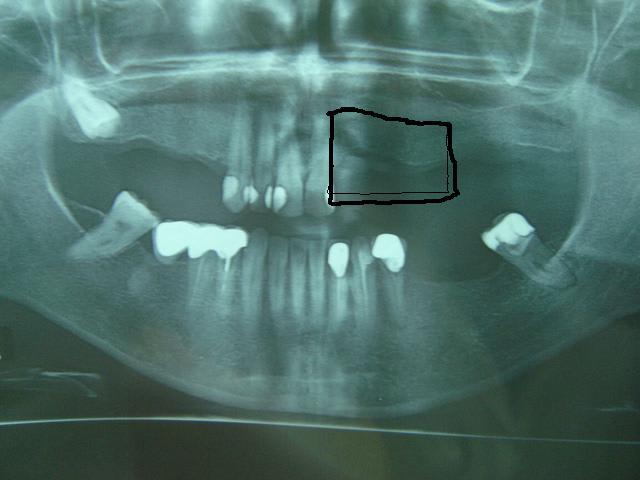

Merci pxav,en réalité c'est une patiente d'une collégue qui demande un avis, et c'est l'image de l'os au niveau 22 ,23 qui m'inquiéte,

c'est l'image de l'os au niveau 22 ,23 qui m'inquiéte,

même chose on a une vue plate.

qu'est ce qui te gène?le manque de hauteur?

c'est vrai que l'on a une impression de tissus osseux "flottant" au dessus de la crête.

Y a t-il eu déjà une greffe ? un comblement type xenogreffe ? une racine comme sous le cantilever en bas....

y'a t il un scan ou au moins des rétro alvéolaire pour préciser ?